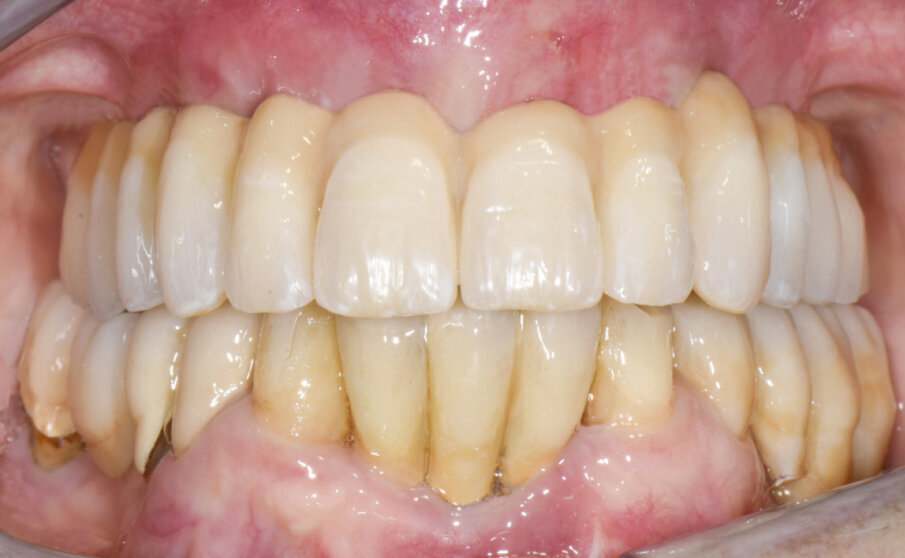

Dopo aver tolto le suture (Fig. 13) e consegnato il Toronto definitivo (Figg. 14, 15), si effettuano due visite di controllo a 2 e 4 mesi di distanza in cui si valutano il rapporto occlusale, il serraggio delle viti di connessione effettuato con chiave dinamometrica tarata a 20 Ncm, RX di controllo e la chiusura degli alloggi delle viti con resina composita (al controllo dopo 4 mesi).

Fig. 14 - Protesi definitiva tipo Toronto in sede (a 7 giorni dall’intervento chirurgico).

Fig. 15 - Protesi definitiva tipo Toronto in sede (a 7 giorni dall’intervento chirurgico).